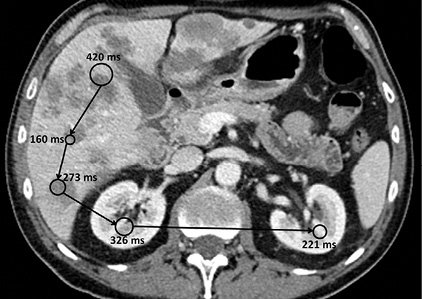

As radiologists interpret studies, their eye movements are composed of fixations — maintaining the gaze on a single location — and saccades, the rapid movements of eyes as they shift between fixation points. “Saccade length and fixation duration are parameters that reflect the moment-to-moment cognitive processing of visual information,” the researchers noted.

“Specialists reacted to the presence of lesions in CT images by longer fixation durations and shorter saccades, and adapted to faster presentation speeds by longer fixation durations and longer saccades,” the researchers reported.

The researchers determined that the decrease in saccade length likely reflects a switch from searching to closer inspection and characterization of a lesion. “The smaller decrease in saccade length for the resident groups indicates that residents are still learning to use this strategy,” the authors said.